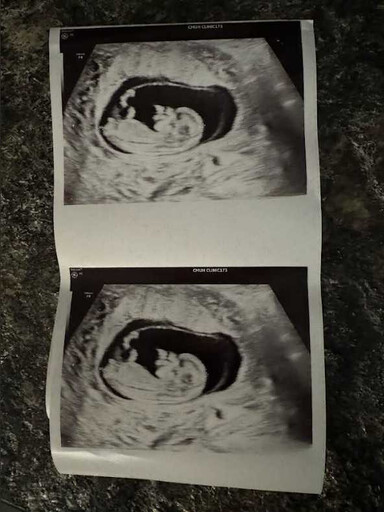

目前懷孕三個多月的芮德預產期為明年一月底二月初左右,芮德透露:「寶寶的小名要知道性別後才取,因為第一胎是剖腹生,所以第二胎也會剖腹產,這次懷第二胎的前1、2個月有低血糖的狀況很明顯,頭暈身體很累,但沒有到孕吐,因為第一胎的時候幾乎沒有什麼不舒服,所以這一胎有稍微感受到懷孕媽媽的辛苦!」